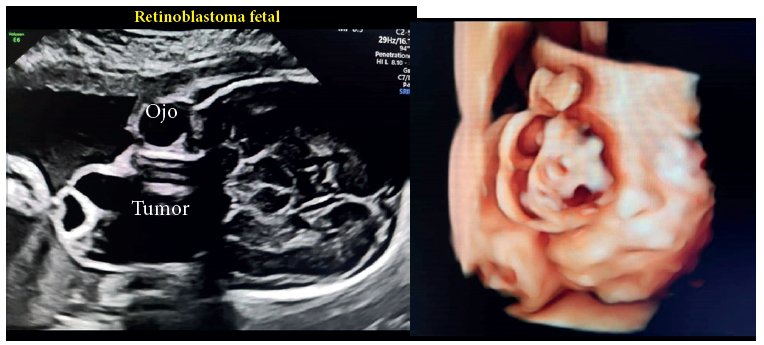

En el corte coronal del cráneo y parte del macizo facial, se observa protrusión de masa semisólida de predominio quístico hacia anterior que ocupa toda la cavidad orbitaria derecha, acompañada de desplazamiento en forma y estructura del globo ocular derecho.

En la imagen 3D, desde el punto de corte coronal. Se evidencia deformación de la estructura del globo ocular derecho con exteriorización de la masa que agranda el mismo de la lesión de manera irregular, con desplazamiento de los párpados y a su borde medial.